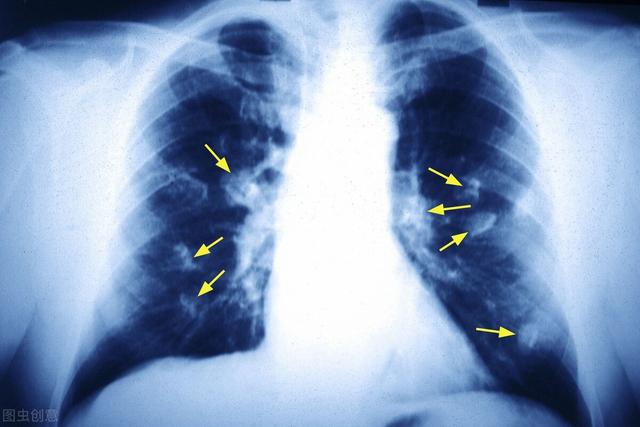

Les nodules pulmonaires sont généralement détectés par radiographie (radiographie du thorax) ou par tomodensitométrie, principalement par tomodensitométrie, car de nombreux petits nodules ne sont pas du tout visibles sur une radiographie du thorax et doivent être détectés par une tomodensitométrie du thorax. C'est ce que se demandent de nombreuses personnes qui font la une des journaux : pourquoi n'y a-t-il rien à redire aux examens médicaux annuels et, soudain, un cancer du poumon se déclare-t-il ? On suppose que l'examen physique a été effectué à l'aide d'une radiographie du thorax plutôt que d'un scanner. Par exemple, si l'on veut voir s'il y a des lésions substantielles (excroissances) dans le foie ou les reins, il faut faire une échographie ou un scanner, et si l'on veut voir les lésions gastro-intestinales, il faut faire une gastroscopie ou une coloscopie, et pas seulement des tests de laboratoire tels que des analyses de sang et d'urine, mais beaucoup de lésions peuvent être normales dans les tests de laboratoire. Ainsi, pour détecter de petites lésions précoces dans les poumons, ou des lésions précancéreuses, en particulier des nodules de verre dépoli, il est recommandé d'effectuer un scanner hélicoïdal à faible dose.